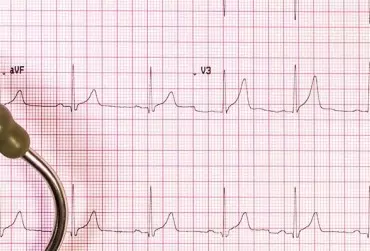

Wrodzony zespół wydłużonego QT (long QT syndrome) to pierwotna elektryczna choroba serca charakteryzująca się nieprawidłowym wydłużeniem, stale lub okresowo, odstępu QT w zapisie EKG oraz predyspozycją do występowania komorowych zaburzeń rytmu serca pod postacią wielokształtnego częstoskurczu komorowego oraz migotania komór. Zespół LQTS spowodowany jest mutacjami w kanałach jonowych w obrębie kardiomiocytów. Częstość występowania szacuje się na 1:5000 do 1:20 000 urodzeń. Rozpoznanie opiera się na podstawie wywiadu od pacjenta, wywiadu rodzinnego, zapisu EKG spoczynkowego oraz metodą Holtera. Leczenie standardowo rozpoczyna się od dużych dawek leków blokujących receptory beta- adrenergiczne.